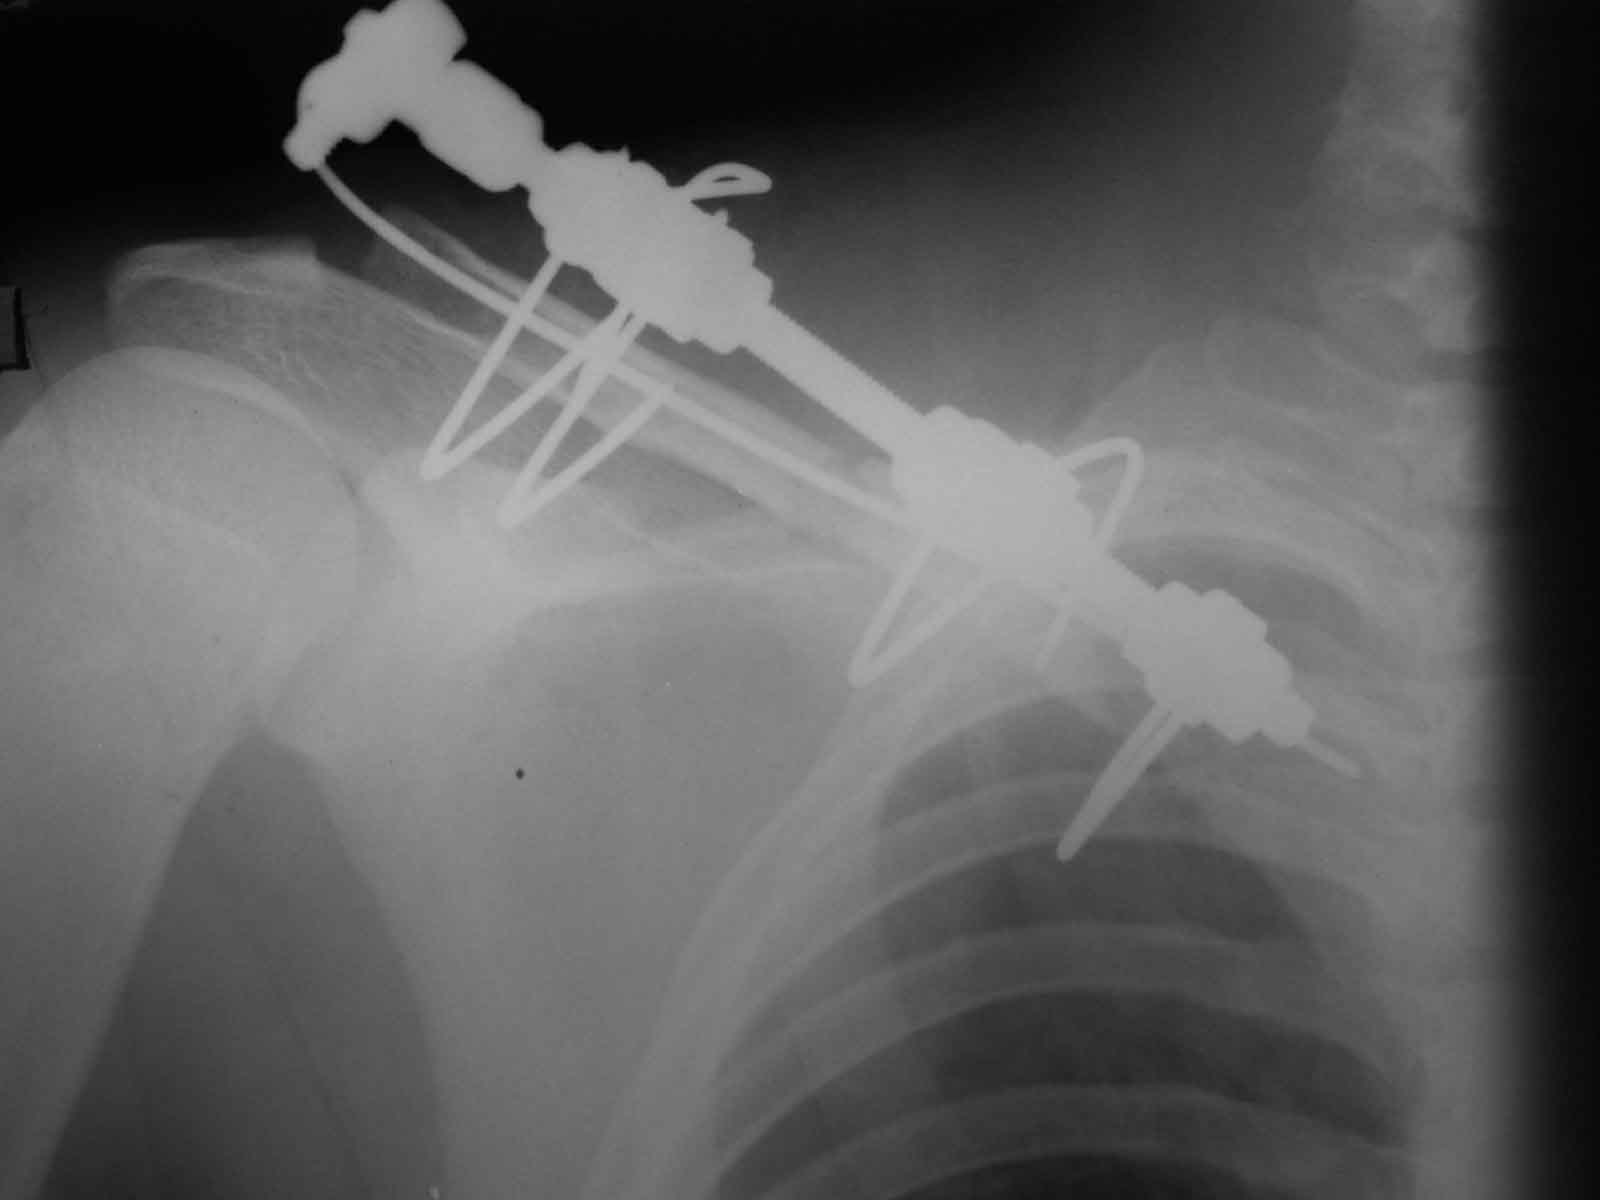

Один из вариантов, что удалось быстро найти, позже еще найду, но схема примерно такая (первое

вложение).

Мужик кочегар, срок нетрудоспособности 7 недель. Наружную конструкцию сняли через 3 недели. Далее без иммобилизации. Погруженную спицу можно убрать и через несколько месяцев, если жить не мешает.

Раньше не погружали, на рентгенограммах и натуре видно (последние 2 вложения). Как вариант спицы в периферическом отломке могут крепится на трехдырочную приставку, что дает возможность компрессии.

Укладка как при переломе, репозиция руками, а когда задавить не удается - однозубым крючком. Практически не открываемся (исключения составляют переломы с линией излома снаружи-внутрь сверху-вниз и острым концом - отломок маленький, а острый конец в мягких тканях путается, не сопоставить) Через акромион в клюциу 2 спицы гоним. две консольные в акромион, еще две в ключицу. Все спицы на стержень. Обычно держиться. Так и вывихи делаем, но там не все выходит, говорил уже.